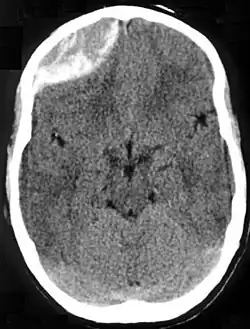

Epidural hematoma as seen on a CT scan with overlying skull fracture. Note the biconvex shaped collection of blood. There is also bruising with bleeding on the opposite side of the brain.

Epidural hematomas usually appear convex in shape because their expansion stops at the skull's sutures, where the dura mater is tightly attached to the skull. Thus, they expand inward toward the brain rather than along the inside of the skull, as occurs in subdural hematomas. Most people also have a skull fracture.[3]